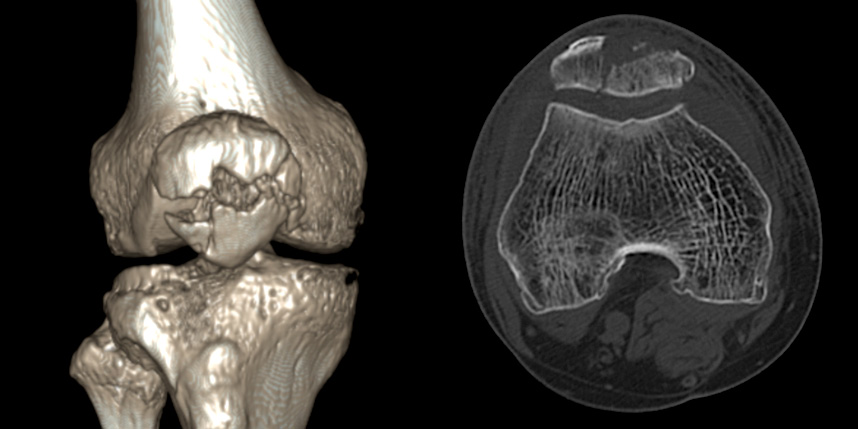

무릎 골절

골절은 정확하게 골절편을 잘 맞추고 고정하는 것이 중요합니다. 특히 관절면을 잘 맞추는 것이 중요합니다.

감탄정형외과는 정확한 초기 진단을 통해 골절 발생일로부터 최대한 빨리 원래의 뼈 상태에 가깝게 원복시키고,

이후 적절한 보호기간과 철저한 재활 치료를 통해 가장 빠르게 일상으로 복귀할 수 있는 코스를 제시해드립니다.